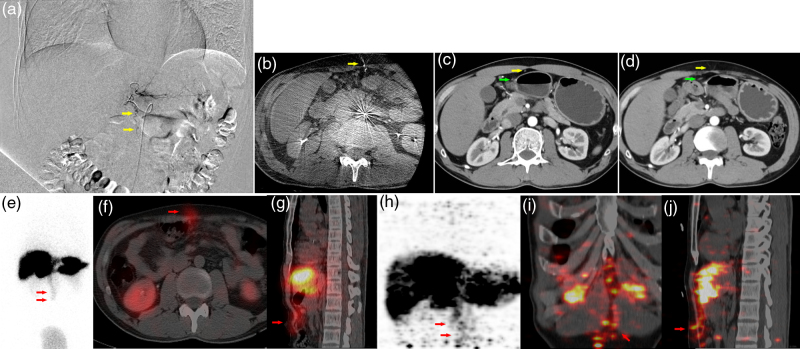

目的:探讨90Y树脂微球选择性内放射治疗(SIRT)中前腹壁(AAW)放射性示踪剂积累的差异模式,采用99mTc-MAA单光子发射计算机断层扫描(SPECT/CT)和90Y正电子发射断层扫描(PET/CT)对前腹壁(AAW)放射性示踪剂积累的影响。材料与方法:回顾性分析2022年8月至2024年11月期间接受SIRT治疗的204例不可切除肝脏恶性肿瘤患者。治疗前评估包括诊断性血管造影和99mTc-MAA成像。治疗后24小时内进行90Y-PET/CT检查微球分布。分析99mTc-MAA图像或90y微球PET/CT图像上AAW积累的患者,并以至少3个月的随访结果作为参考标准。结果:204例患者中,21例(10.3%)在99mTc-MAA图像或90y微球PET/CT图像上显示AAW积累。99mTc-MAA影像与90Y-PET/CT影像一致的有11例(11/21,52.4%),仅在90Y-PET/CT影像上有堆积的有5例(5/21,23.8%),仅在99mTc-MAA影像上有堆积的有5例(5/21,23.8%)。2例患者发现肝镰状动脉(HFA)。4例患者出现轻度腹痛,仅有1例患者出现腹部皮炎,并自行消退。其余患者在随访期间未出现任何相关副作用。结论:aaw相关的并发症罕见且轻微,提示HFA专利可能不被认为是SIRT的禁忌症;然而,99mTc-MAA和90Y-PET/CT之间的不一致强调了治疗后警惕监测的必要性,即使在治疗前没有AAW积累的病例中也是如此。

Materials and methods: A retrospective analysis was conducted on 204 patients with unresectable liver malignancies who underwent SIRT between August 2022 and November 2024. Pretherapeutic evaluation included diagnostic angiography and 99m Tc-MAA imaging. Posttherapeutic 90 Y-PET/CT was performed within 24 h of treatment to verify microspheres distribution. Patients with AAW accumulation on 99m Tc-MAA images or 90 Y-microspheres PET/CT images were analyzed, and follow-up results for at least 3 months served as reference standards.

Results: Among 204 patients, 21 (10.3%) showed AAW accumulation on 99m Tc-MAA images or 90 Y-microspheres PET/CT images. Concordant findings between 99m Tc-MAA images and 90 Y-PET/CT images were observed in 11(11/21, 52.4%) cases, while five cases (5/21, 23.8%) showed accumulation only on 90 Y-PET/CT images, and the other five cases (5/21, 23.8%) showed accumulation only on 99m Tc-MAA images. The hepatic falciform artery (HFA) was found in two patients. Mild abdominal pain was observed in four patients, and only one patient experienced abdominal dermatitis, which resolved spontaneously. The remaining patients did not experience any relevant side effects during the follow-up period.